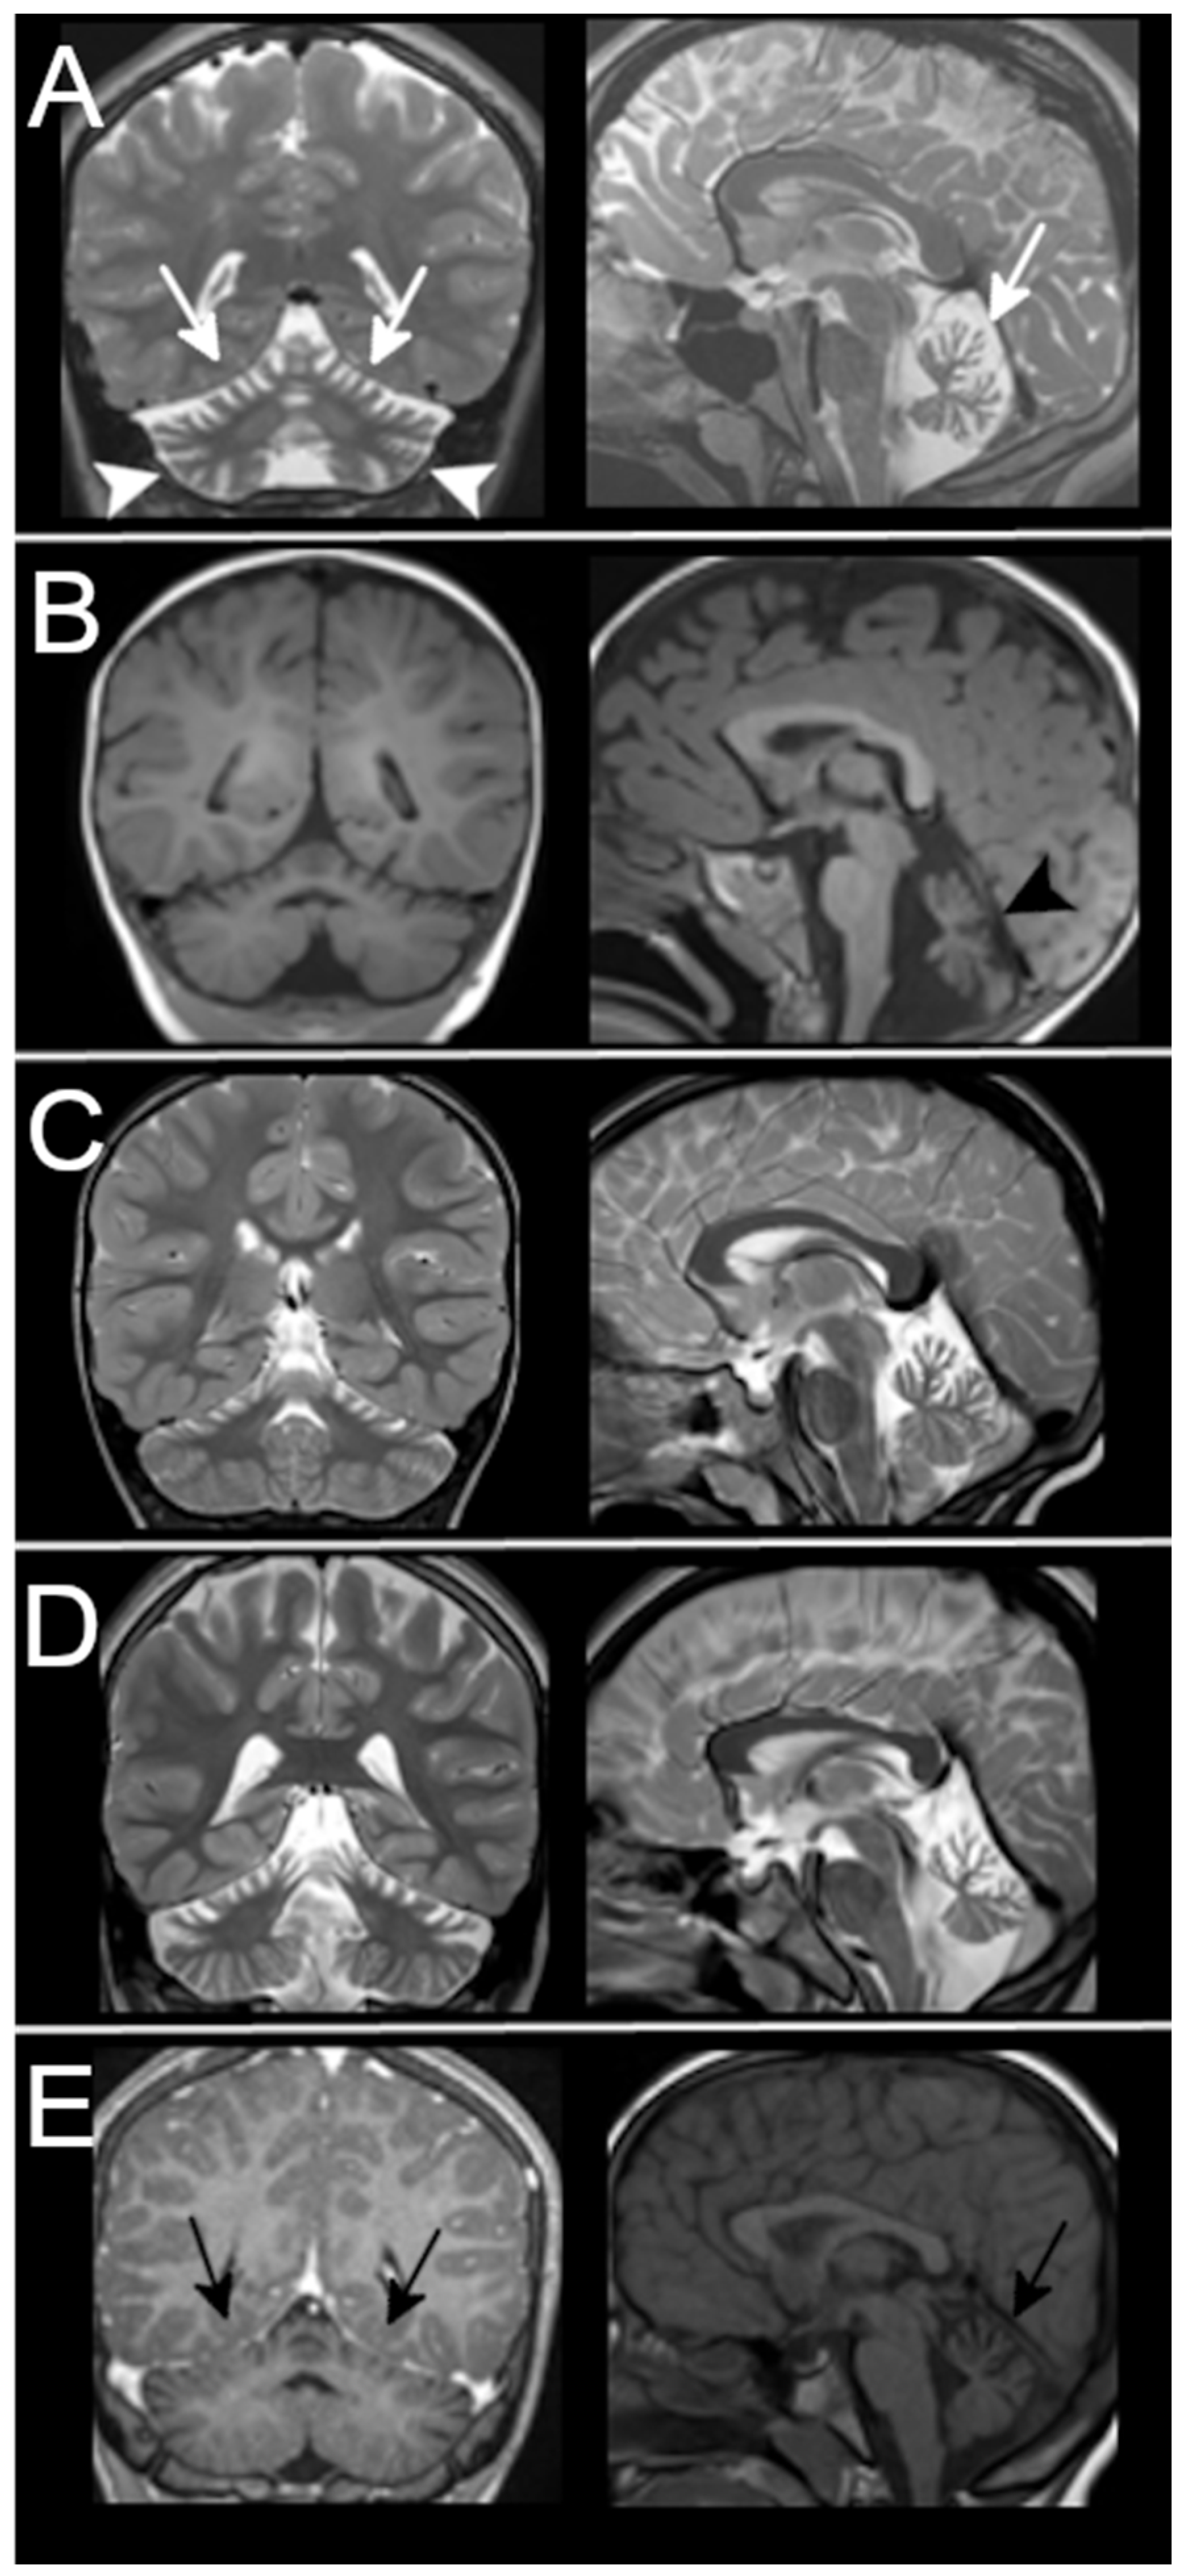

3.3. Neuroradiological Data